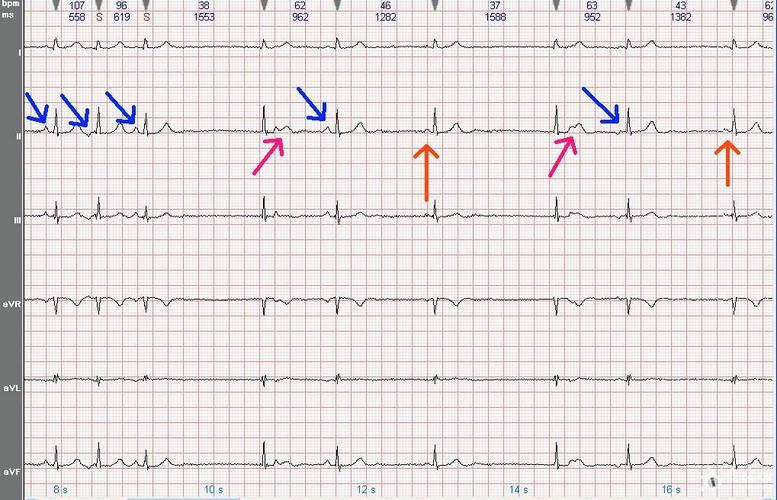

交界性逸搏心律心电图

交界性逸搏心律心电图,加速交界性逸搏心律

心电图知识交界性逸搏及交界逸搏心律

加速交界性逸搏心律

交界性逸搏心律

交界性逸搏

交界性逸搏心电图特点

交界性心律心电图特点